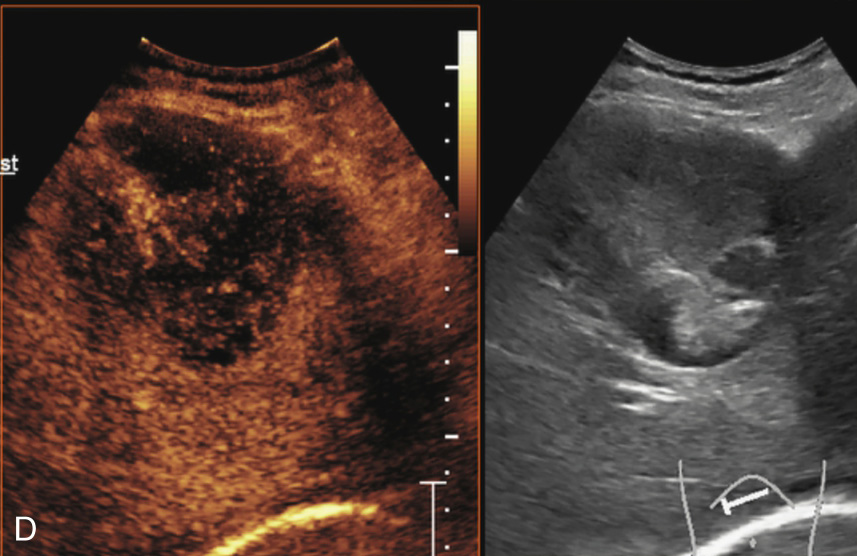

图1-7-6 胆管细胞癌超声造影图像

A.造影剂注入14s周边不规则环状增强;B.35s病灶内造影剂开始消退呈低增强

图1-7-6(续)

C、D.门脉期及延迟期造影剂持续消退呈低增强